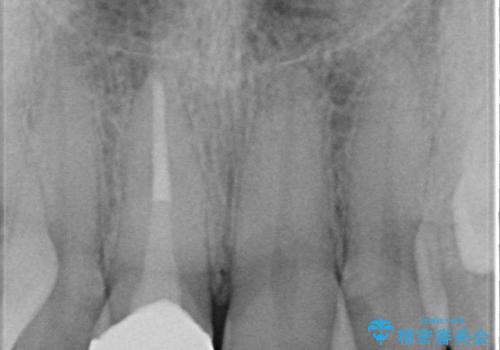

前歯の治療。再根管治療~セラミッククラウン